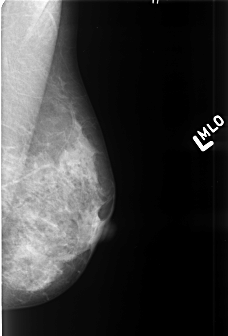

Digital Database for Screening Mammography

Volume: benign_06 Case: B-3419-1

B_3419_1.LEFT_MLO

LEFT_CC LINES 4424 PIXELS_PER_LINE 3032 BITS_PER_PIXEL 12 RESOLUTION 50 NON_OVERLAY